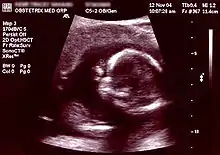

Ecografia

A ecografia é um exame seguro que não implica nenhum risco para a grávida ou para o feto e que permite detectar algumas doenças congénitas durante a fase inicial da gravidez, estimar com maior precisão a idade gestacional e a data prevista de parto e detetar uma gravidez múltipla.[74] A partir das cinco semanas e meia de gestação já é possível observar o embrião. Quando este atinge 5mm é possível observar o batimento cardíaco por ecografia pélvica, embora em alguns casos só seja visível quando atinge os 7mm, o que acontece por volta da 7ª semana.[75] As recomendações internacionais de saúde pública recomendam que seja realizada pelo menos uma ecografia de rotina a todas as grávidas entre as 18 e as 22 semanas de gestação (ecografia do segundo trimestre) e, em países com recursos, que seja também realizada uma ecografia de rotina entre as 11 semanas e as 13 semanas e seis dias de idade gestacional (ecografia do primeiro trimestre). Em alguns países realiza-se ainda uma ecografia de rotina entre as 30 e as 32 semanas (ecografia do terceiro trimestre). Em todas as ecografias de rotina de uma gravidez de baixo risco são avaliados o número de fetos e placentas, a atividade cardíaca, os movimentos fetais, a localização da placenta, a quantidade de líquido amniótico e os valores biométricos. Para além destes parâmetros gerais, em cada trimestre são também avaliados parâmetros específicos.[76][77][78][79]

Na ecografia do primeiro trimestre são geralmente avaliados o comprimento crânio-caudal, a frequência cardíaca do feto, a medida da translucência da nuca, se gémeos partilham ou não a placenta (corionicidade) e a anatomia do feto (pólo cefálico, coluna vertebral, estômago, parede abdominal e membros).[79] O comprimento crânio-caudal permite determinar a idade gestacional com uma precisão ligeiramente superior aos cálculos com base no último período menstrual. Uma vez determinada a idade gestacional por ecografia, não será alterada até ao fim da gravidez.[80] Durante a ecografia do primeiro trimestre é também calculado o risco de trissomia 21. Este risco é calculado através da ponderação conjunta do valor de translucência da nuca medido por ecografia, da idade da mãe e, sempre que possível, do rastreio por análises clínicas da fração livre da gonadotrofina coriónica humana e da proteína plasmática associada à gravidez. Este rastreio combinado identifica 90% dos casos de trissomia 21 e outras principais doenças congénitas.[81]

A ecografia do segundo semestre, ou ecografia morfológica, para além de confirmar alguns dados do primeiro trimestre, destina-se principalmente a identificar malformações do feto. São avaliados o contorno craniano e cérebro, face e pescoço, coração, pulmões, abdómen, coluna vertebral, membros, cordão umbilical e genitais externos. É possível distinguir o sexo do feto por ecografia a partir das 11 semanas de gestação. No entanto, só a partir das 13 semanas é que é possível fazê-lo com uma precisão entre 99% e 100%.[82] Na ecografia do terceiro trimestre são avaliados a apresentação fetal, o perímetro cefálico, perímetro abdominal, comprimento do fémur e vários parâmetros biofísicos.[79]